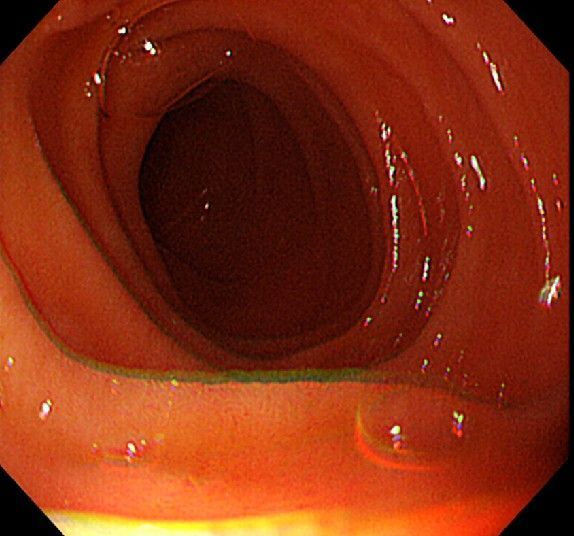

위 내시경을 찍었는데 위염 종류 사진을 알 수 있을까요? (사진 많습니다..)

한달 전 쯤에 소화불량과 속쓰림이 3개월 동안 약을 먹어도 낫지 않아 위 내시경을 찍었는데 위에 염증이 많이 있다는 이야기를 들었습니다...그런데 상태가 얼마나 안 좋은지 어떤 종류의 위염인지에 대해서는 물어봐도 안 알려주셔서 여기에라도 올려서 여쭈어봅니다... 제 상태가 얼마나 심각한 걸까요..

• 2번 째 사진

안녕하세요. 이욱현 의사입니다. 심각한 상황이 아닌 것으로 보이고 특별한 종류의 위염도 아닌 것으로 보입니다. 너무 걱정하지 않으셔도 되겠습니다.

사진상으로 보아서는 정상에 가까운 점막상태이거나 약간의 표재성 위염이 있는 정도로 보입니다.

홍반성 위염이 있으며 경증의 역류성 식도염이 있습니다

위내시경상으로는 특이소견이 없다고 보셔도 됩니다